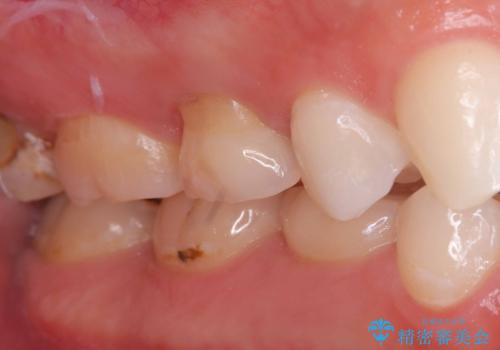

- 「歯がたまに痛む」を主訴に来院された患者様です。 見た目では齲窩が無いように見えますが、レントゲンを撮ると神経の近くまで達する深い虫歯だとわかりました。

虫歯を除去後セラミックインレーで治療を行いました。隣の子どもの歯のEも虫歯になっていたので同時に治療を行いました。

神経の近くまで虫歯が広がっていましたが、神経を保存して治療を行うことが出来ました。

見た目も凄く綺麗になり痛みも無く経過も良好なので、患者様も大変ご満足されていました。

Eに関してはCRで修復を行っています。